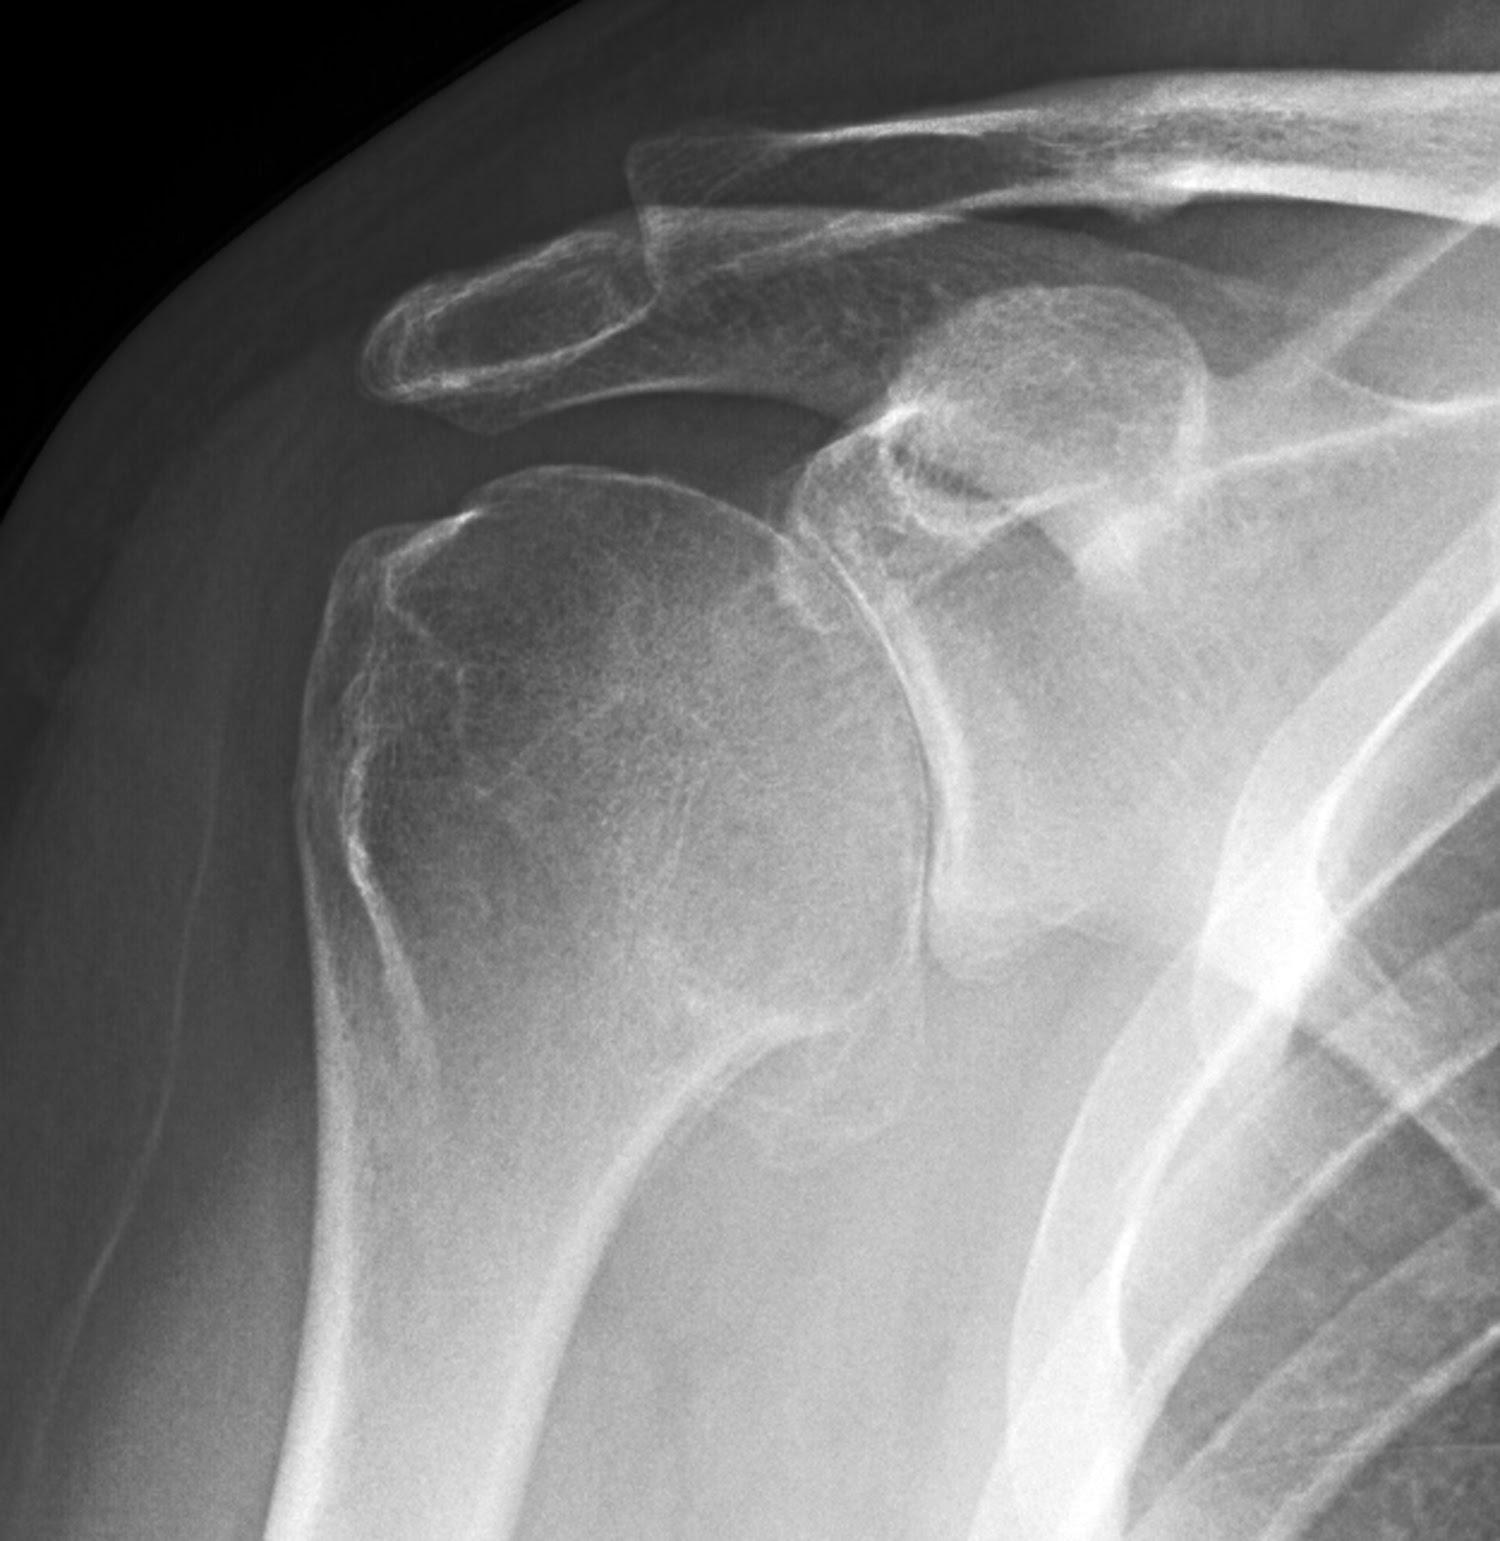

Shoulder Dislocation XRay at John Wiles blog

Anterior Shoulder Dislocation X Ray HopeanceHawkins Can An X Ray Show Shoulder Problems shoulder radiographs are often the only imaging exam necessary for the evaluation of acute shoulder trauma,. Magnetic resonance imaging (mri) scans and ultrasound. what to expect. A shoulder arthrogram is a technique that uses contrast dye to identify specific shoulder injuries. Can An X Ray Show Shoulder Problems.